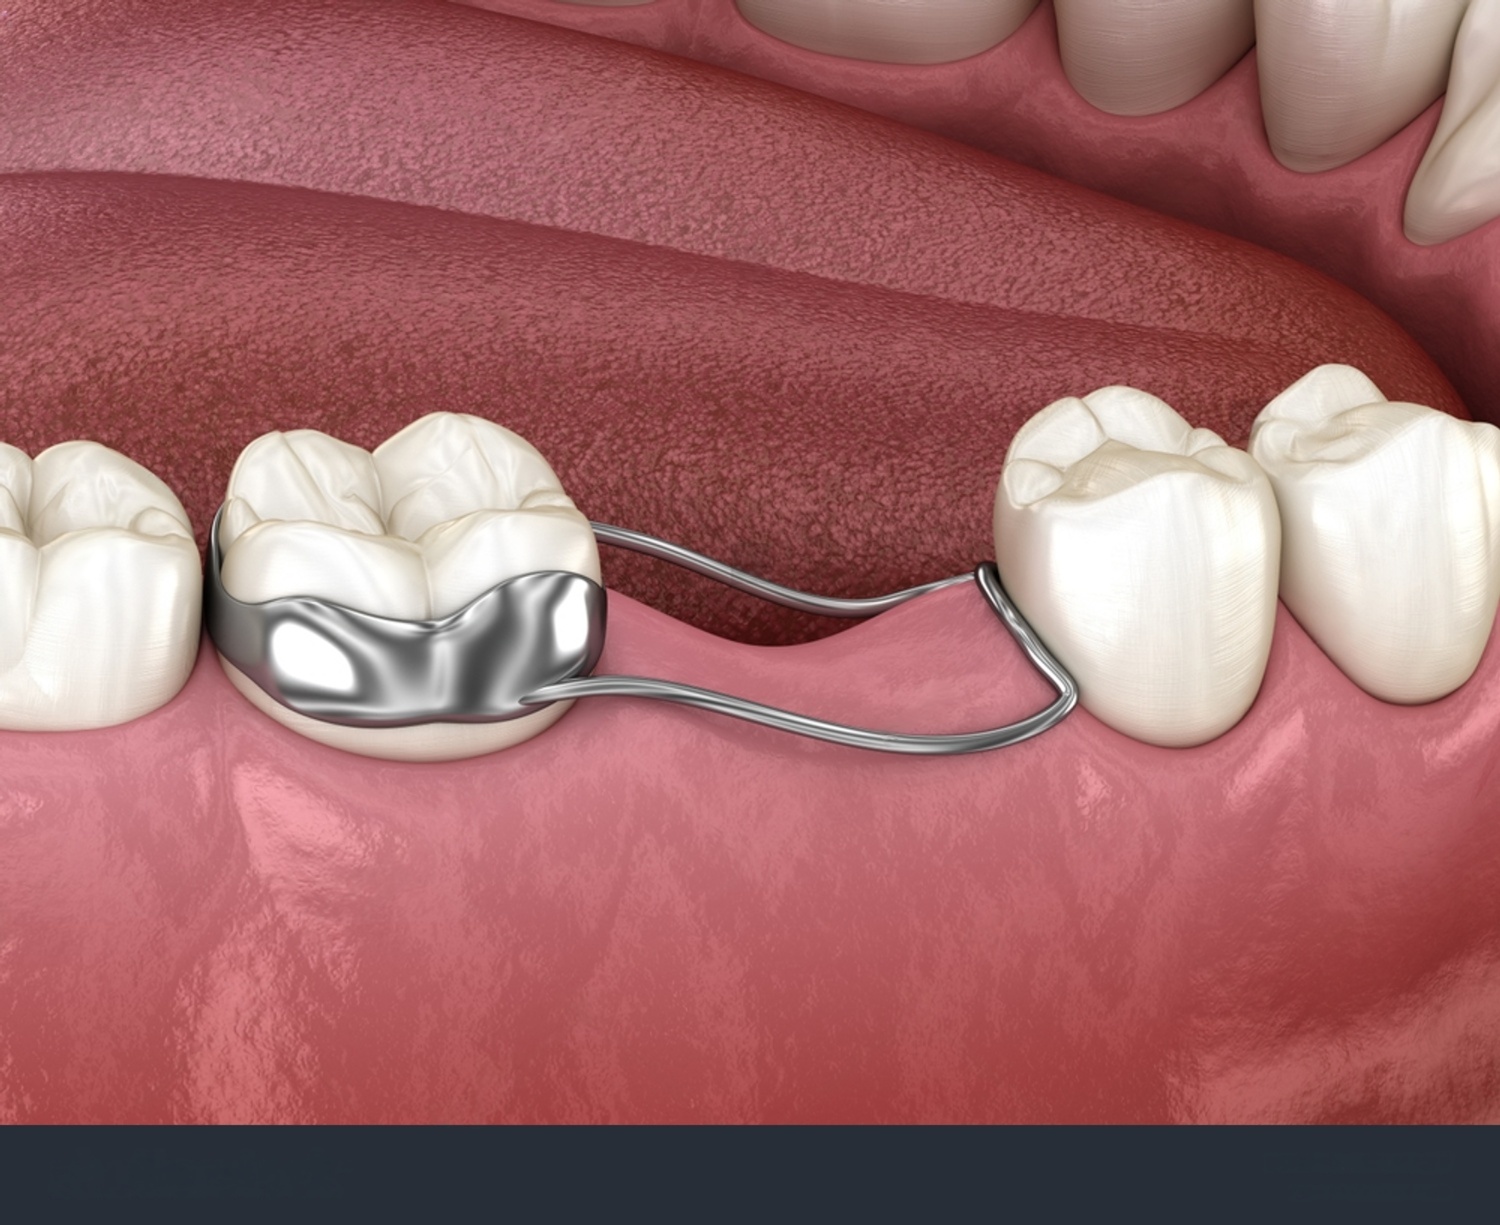

Space Maintainers

We help preserve proper space when a baby tooth is lost too early. They guide healthy alignment and ensure permanent teeth grow in correctly.